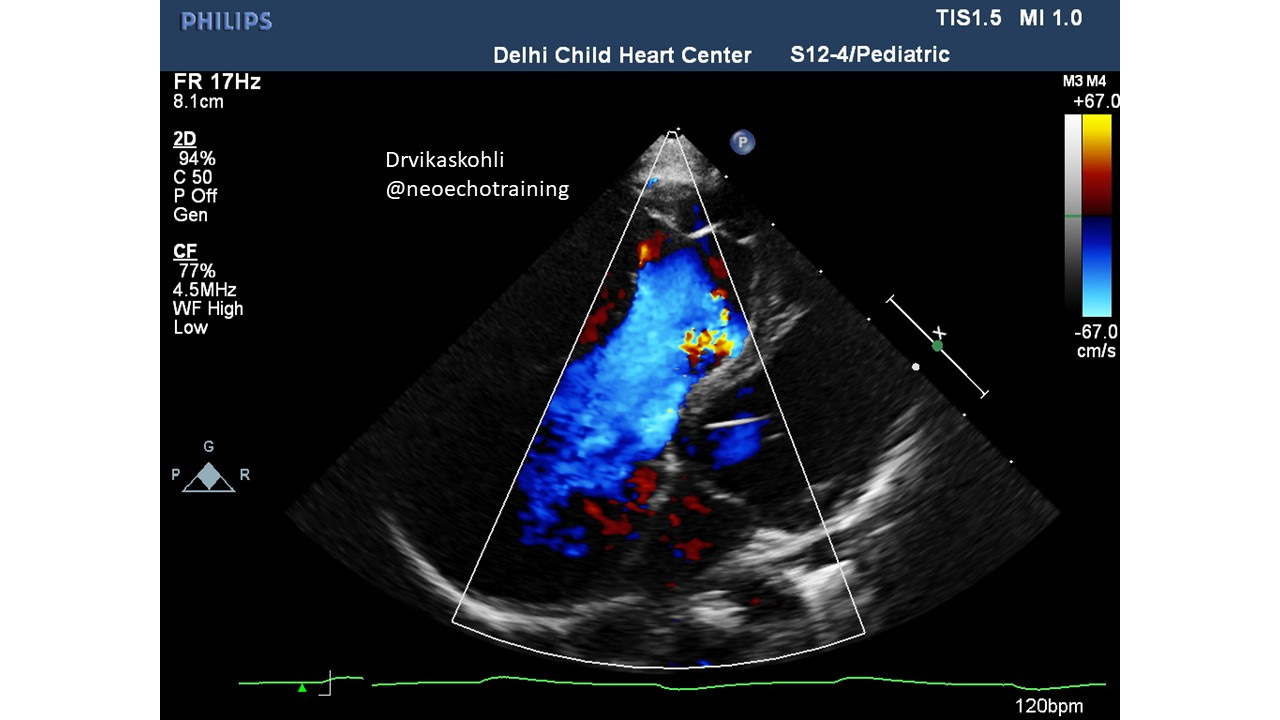

This is associated with severe TR which is normal pressure TR.

The RV from the true tricuspid attachment to the new septal leaflet attachment is referred to as Atrialized RV.